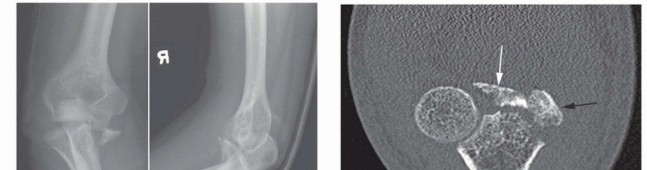

Meticulous preoperative planning is the cornerstone of a successful surgical outcome in elbow fracture-dislocations. High-quality plain radiographs in the anteroposterior (AP) and lateral planes must be obtained before and after any closed reduction attempts. However, cast material and overlapping osseous structures often obscure critical bony detail. Therefore, computed tomography (CT) scanning with thin cuts, multiplanar reformatted images, and three-dimensional (3-D) reconstructions is considered the gold standard and is mandatory for surgical planning. 3-D CT allows the surgeon to precisely understand the size, comminution, and spatial orientation of the coronoid and radial head fragments, dictating whether primary osteosynthesis is feasible or if arthroplasty will be required.

Coronoid fractures are equally critical to evaluate, as the coronoid provides the anterior buttress preventing posterior subluxation of the ulna. These have been traditionally classified by Regan and Morrey: Type I (tip avulsions, often representing capsular avulsions rather than true osseous stabilizers), Type II (less than 50% of the coronoid height), and Type III (more than 50% of the coronoid, often involving the sublime tubercle and MCL insertion). However, modern biomechanical understanding emphasizes the anteromedial facet fracture, a distinct entity caused by a primary varus force. The medial facet is paramount for varus stability of the elbow. These fractures are inherently unstable and are best treated with open reduction and internal fixation utilizing a medial buttress plate, as failure to recognize and stabilize the anteromedial facet will lead to rapid articular wear and chronic varus instability.